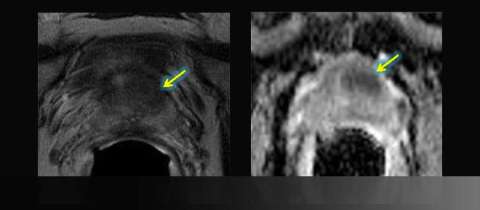

- Hypointense left anterior lesion with restricted diffusion is moderately suspicious, not in biopsy zone

LEFT: Axial T2-weighted image: asymmetric anterior low signal

RIGHT: Apparent diffusion coefficient (ADC) map: focal restricted diffusion